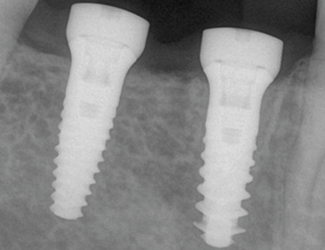

Implantatbehandling utfördes med Straumann TLX SLActive 4,5 x 10 mm RT i region 45 samt Straumann TLC SLActive 4,5 x 10 mm RT i region 46. Implantaten installerades med ett insättningsmoment på 45 Ncm. Vid initial ISQ-mätning uppvisade båda implantaten ett värde på 79, vilket indikerade god primär stabilitet. Efter åtta veckors läkning bedömdes implantaten som stabila för avtryckstagning inför permanent protetisk rehabilitering, med ett uppmätt ISQ-värde på 88.

2. Implantatinstallation region 45 & 46.

3. Mätning av ISQ som visar god stabilitet.